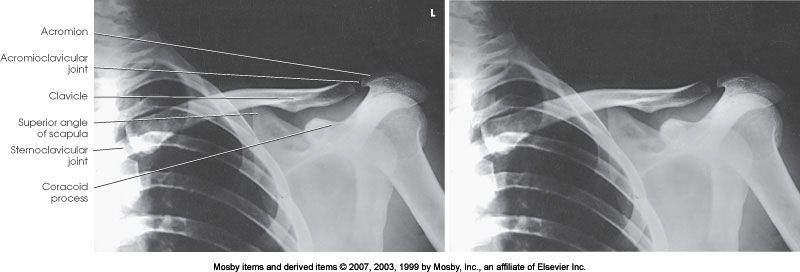

AP Axial Clavicle

What position is demonstrated?

PA Clavicle

What articulation is demonstrated

AC Joint